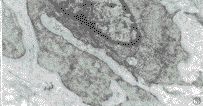

心臟粘液瘤腫瘤大小不一,多有蒂與心房或心室壁相連,外形多樣,外觀富有光澤,呈半透明膠凍狀。切面呈實質性,間有斑片狀出血區及充滿凝血塊的小囊腔。顯微鏡下可見腫瘤細胞呈星芒狀、梭形、圓形或不規則形,散在或呈閉索狀分布於大量粘液樣基質中,胞核多為單核也可呈多核瘤巨細胞。粘液肉瘤瘤細胞形態不一,胞核大,染色深,可見核分裂,瘤細胞可浸潤至小血管內形成瘤栓。